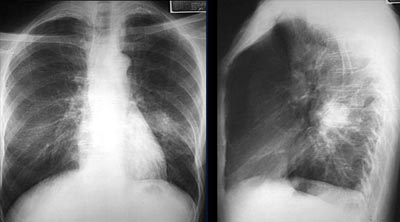

Лабораторные данные позволяют в ранней стадии определить пневмонию. В общем анализе крови наблюдается лейкоцитоз (увеличение количества лейкоцитов больше нормы), повышение СОЭ. Основной метод, который поможет распознать пневмонию у ребенка – это рентгенография органов грудной клетки. На снимке определяет воспаление легких наличие тени в локальном участке ткани или затемнения органа с одной или двух сторон.

Основным методом, подтверждающим диагноз, является рентгенография органов грудной клетки.

На снимке проявляется пневмония в виде тени. Она имеет треугольную форму и четкие границы. Общий анализ крови при пневмонии имеет признаки воспаления — это ускоренное СОЭ и лейкоцитоз.